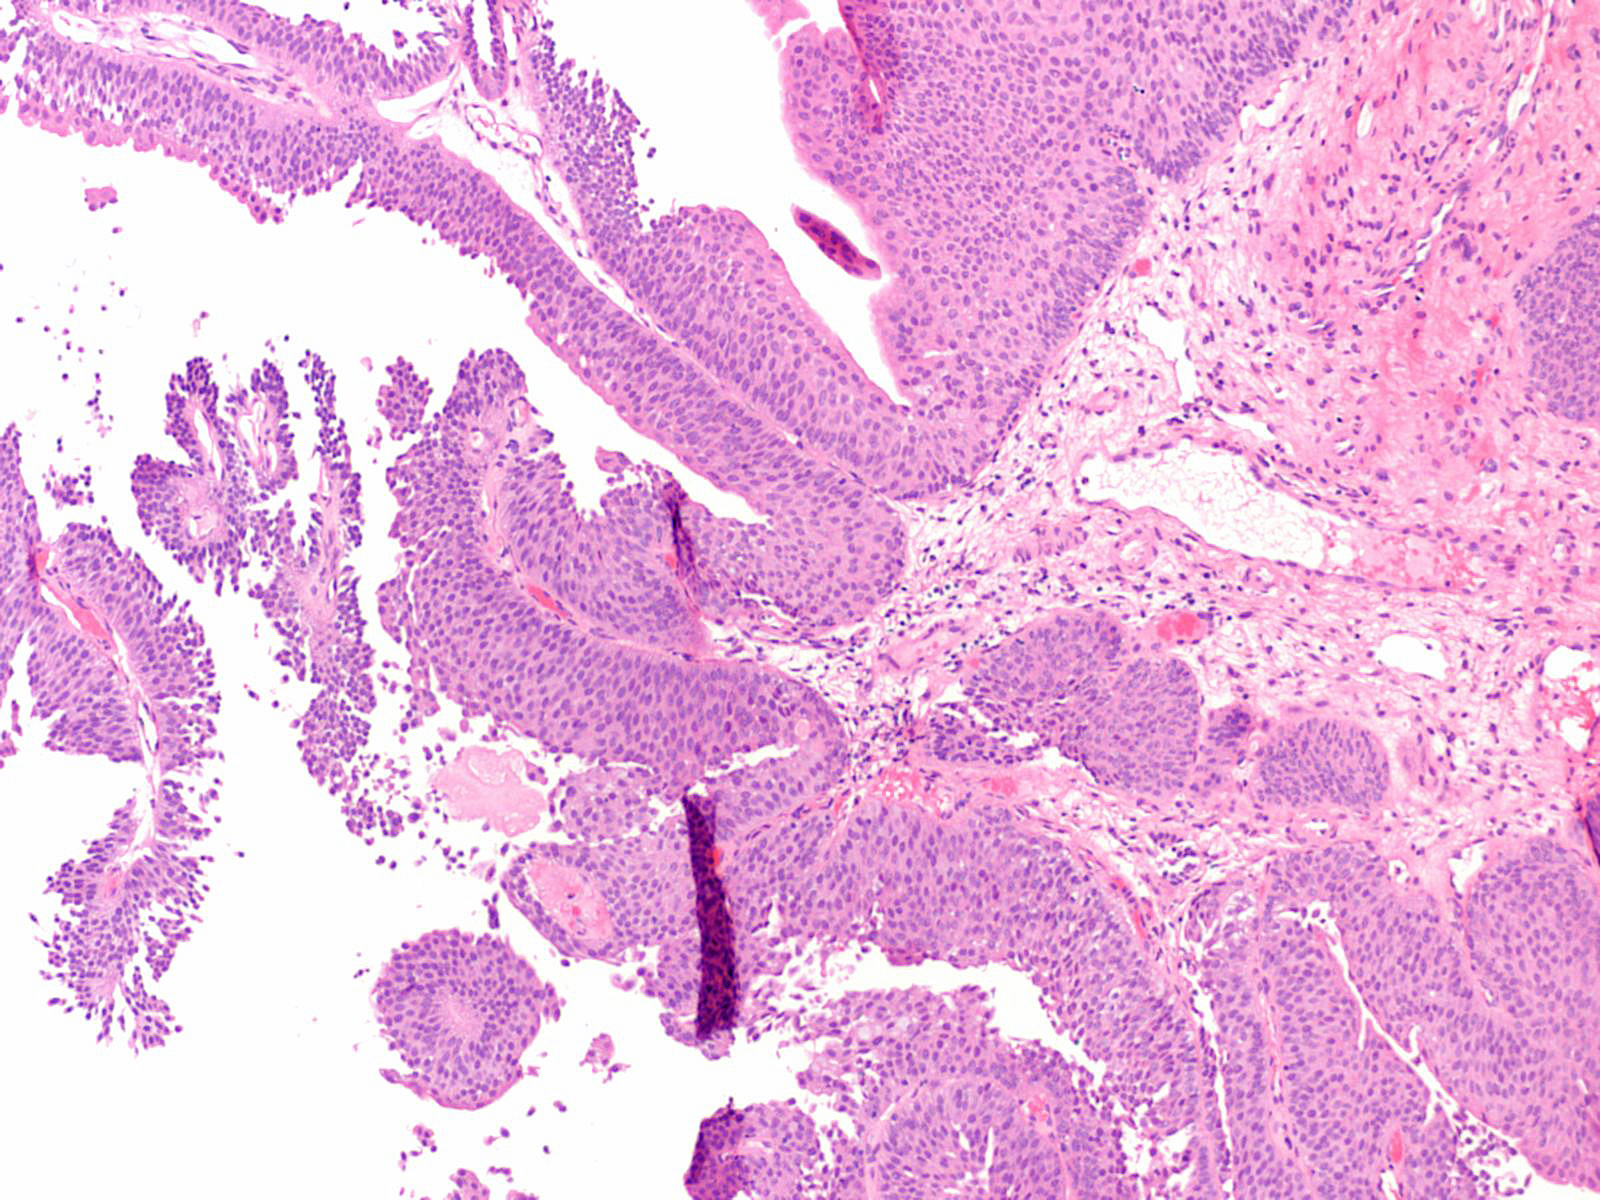

Bladder Papillary Lesions

Case ID: 149